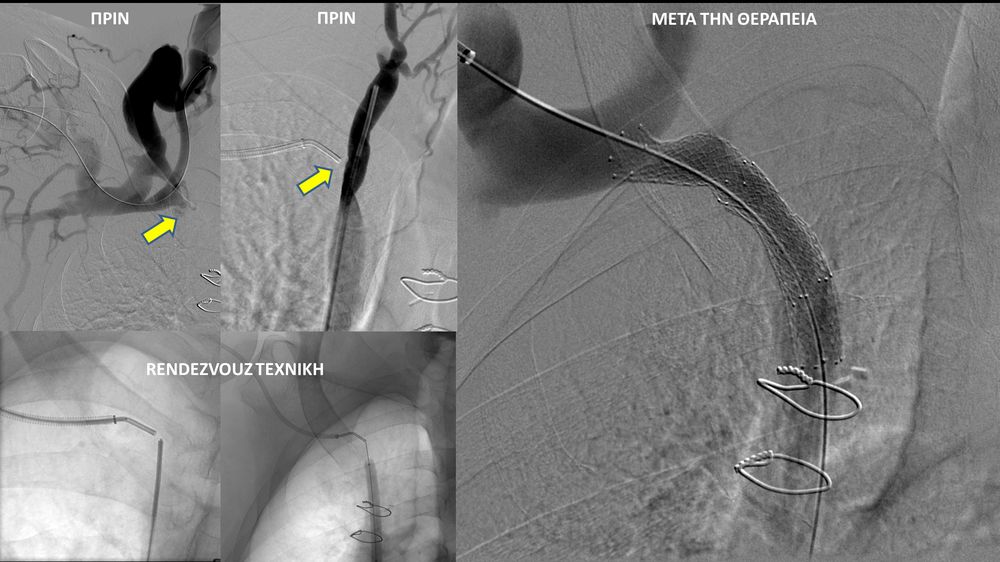

- Φιστουλογραφία ονομάζεται η αγγειογραφία των μοσχευμάτων-fistula αιμοκάθαρσης. Είναι είναι μια ελάχιστα επεμβατική διαγνωστική εξέταση που ενδείκνυται για την ανάδειξη στενώσεων που θέτουν σε κίνδυνο την λειτουργία της αγγειακής πρόσβασης και δεν επιτρέπουν την επαρκή αιμοκάθαρση. Η εξέταση διενεργείται με τη χρήση αγγειογράφου και ιωδιούχου σκιαγραφικού μέσου.

- Η φιστουλοπλαστική είναι μια ελάχιστα επεμβατική μέθοδος αντιμετώπισης της δυσλειτουργίας των αρτηριοφλεβικών προσβάσεων αιμοκάθαρσης (μοσχευμάτων ή fistula) λόγω αρτηριακών ή φλεβικών στενώσεων, χωρίς να χρειαστεί χειρουργείο. Η φιστουλοπλαστική διενεργείται σε αγγειογραφική σουίτα με συνθήκες αποστείρωσης και υπό τοπική αναισθησία, ενώ η θεραπεία περιλαμβάνει συνήθως την διαστολή της αγγειακής στένωσης με ειδικό «μπαλονάκι» υψηλών πιέσεων. Στη περιπτωση όπου οι αγγειακές διαστολές δεν επιφέρουν το επιθυμητό αποτέλεσμα, τοποθετούνται μεταλλικές ενδοπροθέσεις (stents).